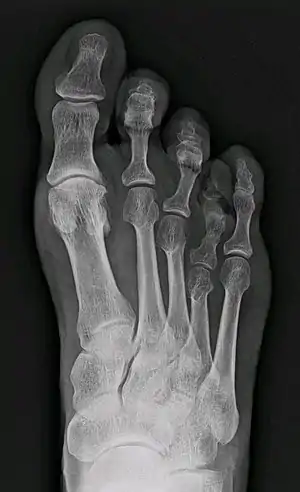

| X-ray of congenital brachymetatarsia involving fourth metatarsal bone | |